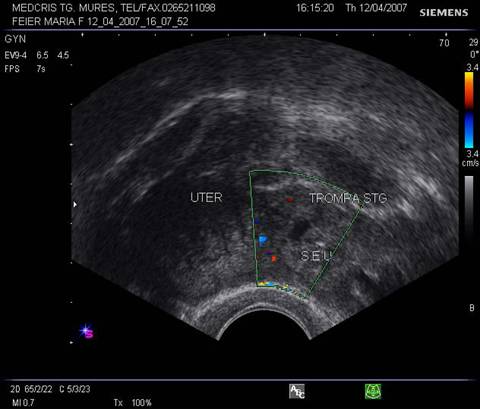

Fig nr 62 Sectiune transversala la nivel corpului uterin , la ecografia transvaginala. Parauterin, in trompa stg., se evidentiaza o formatiune inomogena cu ecou hipoecogen relativ central

![]()

Fig nr 63

Aceeasi sarcina extrauterina oprita in evolutie ca in fig precedenta, marita cu

zoom. Se observa ( cu sageata ) un

embrion pe cale de liza ,situat decliv in sacul gestational .